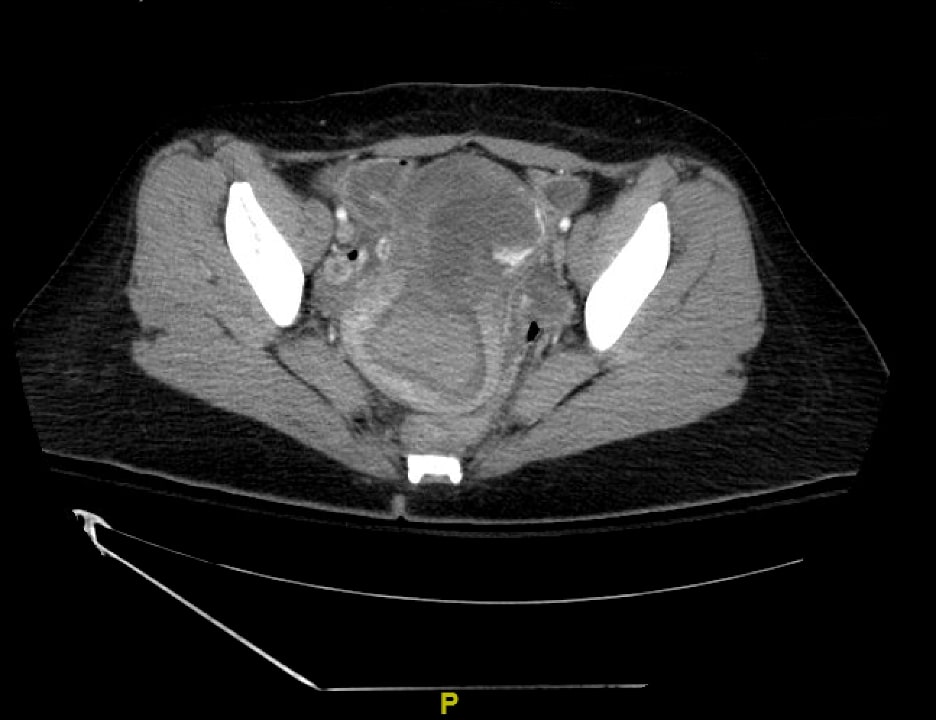

Uterine perforation is a rare but potentially life-threatening complication of gynecologic procedures. Serious complications include hemorrhage, infection, and injury to surrounding organ systems (eg, gastrointestinal, urological, vascular, etc.). Risk factors include advanced maternal age, prior gynecologic surgeries, and other anatomical features that impact the difficulty of accessing the uterine cavity. In this case report, we discuss a patient who presented to the emergency department (ED) with diffuse abdominal pain and vaginal bleeding that occurred after an elective dilation and curettage (D&C) for a termination of pregnancy. The diagnosis was suspected clinically and confirmed by imaging including ultrasound (US) and computed tomography (CT) of the abdomen and pelvis. The patient was managed operatively with a multidisciplinary approach including Gynecology, General Surgery, and Urology. The patient was stabilized and eventually discharged. Uterine perforation should be included in the differential for patients with a history of recent gynecologic instrumentation presenting with abdominal pain and vaginal bleeding. The stabilization of these patients requires aggressive volume resuscitation, controlling the source of bleeding, and emergent surgical consultation.

Topics: Gynecology, vaginal bleeding, ultrasound, computed tomography.